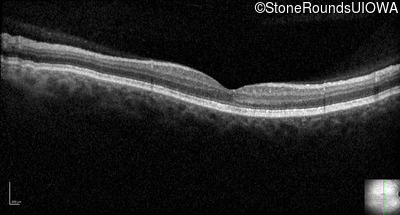

Optical Coherence Tomography - Right - 20/160 -1

Exemplar / OCT Stack